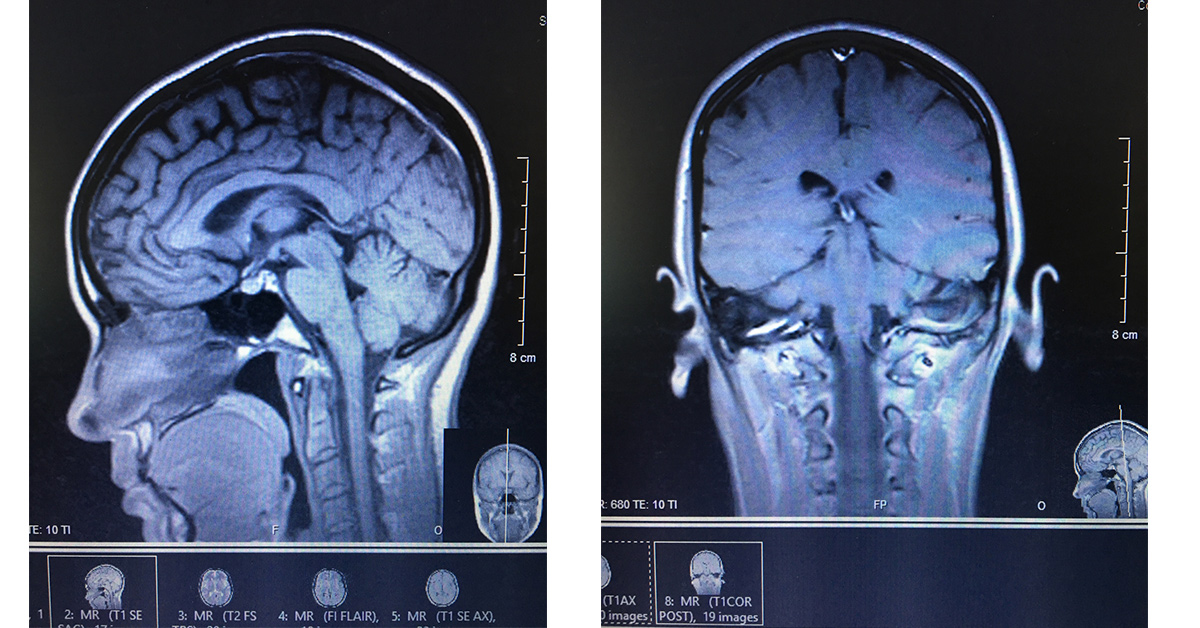

Grief Brain Eighteen months ago my brain broke as a result of an incredible loss I experienced. My late husband’s…